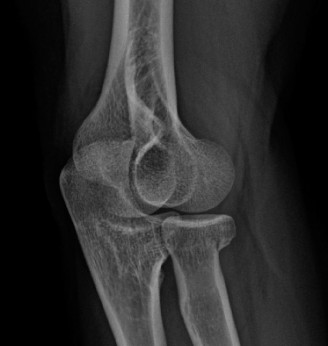

The challenges associated with treating an in-season athlete? CASE 12 A 28-year-old, recreational athlete presents to your clinic with shoulder pain and a history of multiple subluxations in the past. He describes a recent frank dislocation that had to be “popped” back in place on the field. His imaging is shown below (Fig. 2–34).

Figure 2–34

The correct answer is (A). The question describes a young, athletic patient with a history of multiple instability events, and as such, he is very prone to subsequent instability events. Although the initial treatment involves physical therapy, it is likely that this patient will require surgical stabilization. The image demonstrates a located shoulder with a small Hill–Sachs lesion and no significant glenoid bone loss, making capsulolabral repair the appropriate treatment option. For a patient with a failed capsulolabral repair or significant anterior bone loss (>20%), a Latarjet procedure is employed. A Remplissage (Answer C) is indicated for a large Hill–Sachs lesion, which is not seen on the image provided. A Putti–Platt procedure (Answer E) involves a vest-over-pants imbrication with the goal of shortening the subscapularis and anterior capsule. This procedure was historically used for anterior instability but has been replaced by more modern techniques as it causes a significant restriction of external rotation.